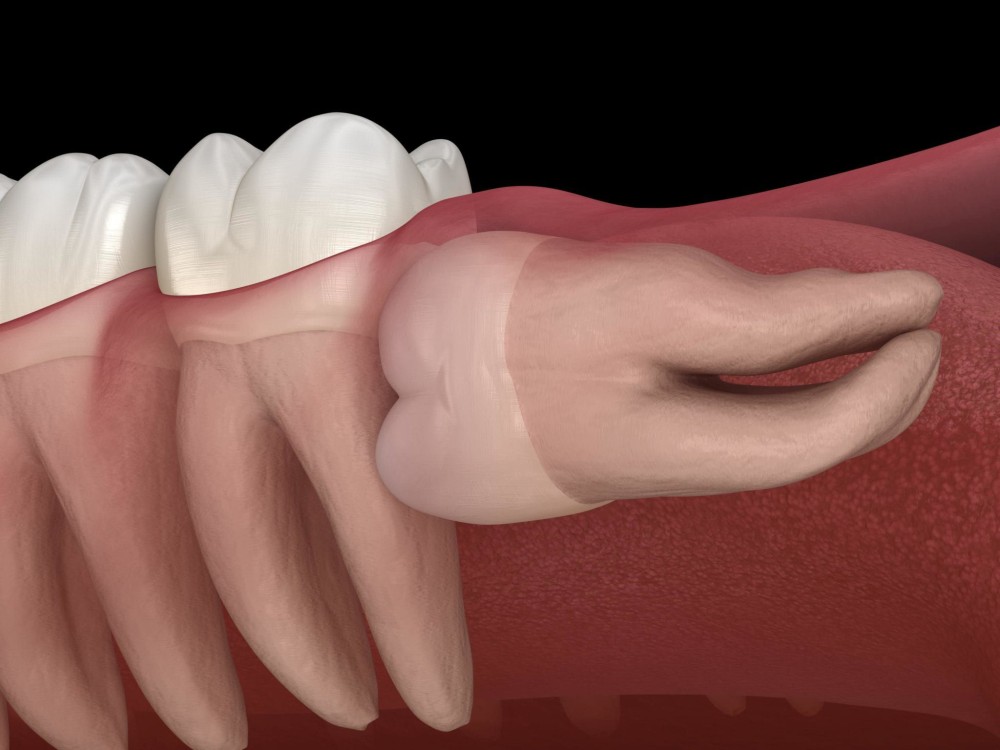

They can get partially stuck in your gums or grow at an angle. This is called an impacted wisdom tooth. Even impacted wisdom teeth don’t always need to be taken out if they aren’t causing any symptoms.

Sometimes though, the way an impacted wisdom tooth is positioned can make it easy for food and bacteria to get trapped around the gum. This can lead to swollen and sore gums (pericoronitis), tooth decay and infection. If you’re having problems such as these, your dentist may recommend taking the impacted tooth out.

The procedure for removing your wisdom teeth will vary, depending on how difficult your teeth are to take out. Upper wisdom teeth are usually easier to remove than lower ones. Your dentist can tell you exactly what to expect.